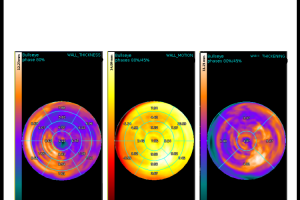

Šta je MSCT koronarografija?

MSCT koronarografija je brza, precizna i neinvazivna metoda snimanja koja nam omogućava jasan uvid u stanje vaših koronarnih arterija. Pomoću najsavremenije CT tehnologije, možemo detaljno analizirati protok krvi i identificirati eventualna suženja ili blokade.

3. Precizna dijagnostika: Najsavremenija tehnologija omogućuje nam otkrivanje čak i najmanjih promjena u koronarnim arterijama.